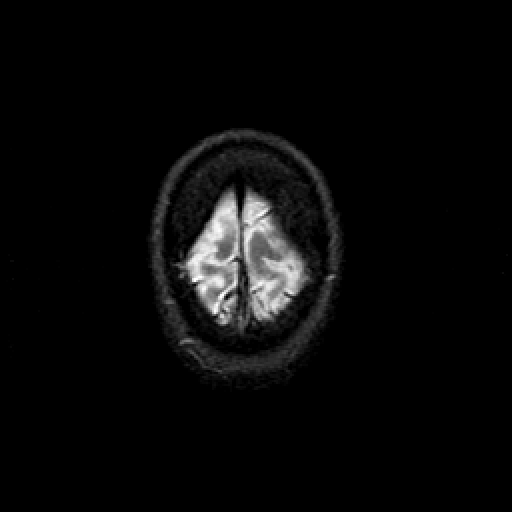

T2-weighted structural MR: Slice 49

Slice 49